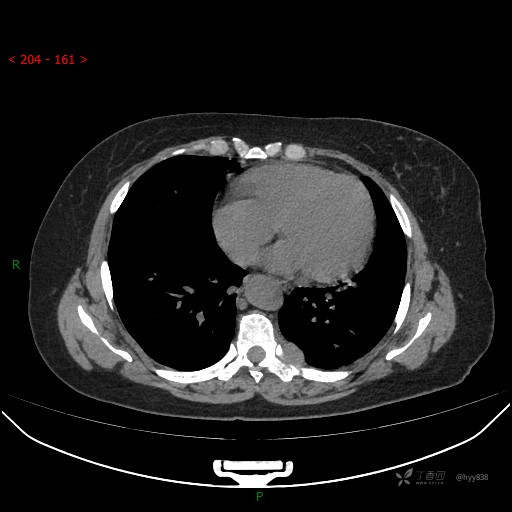

胸部CT平扫